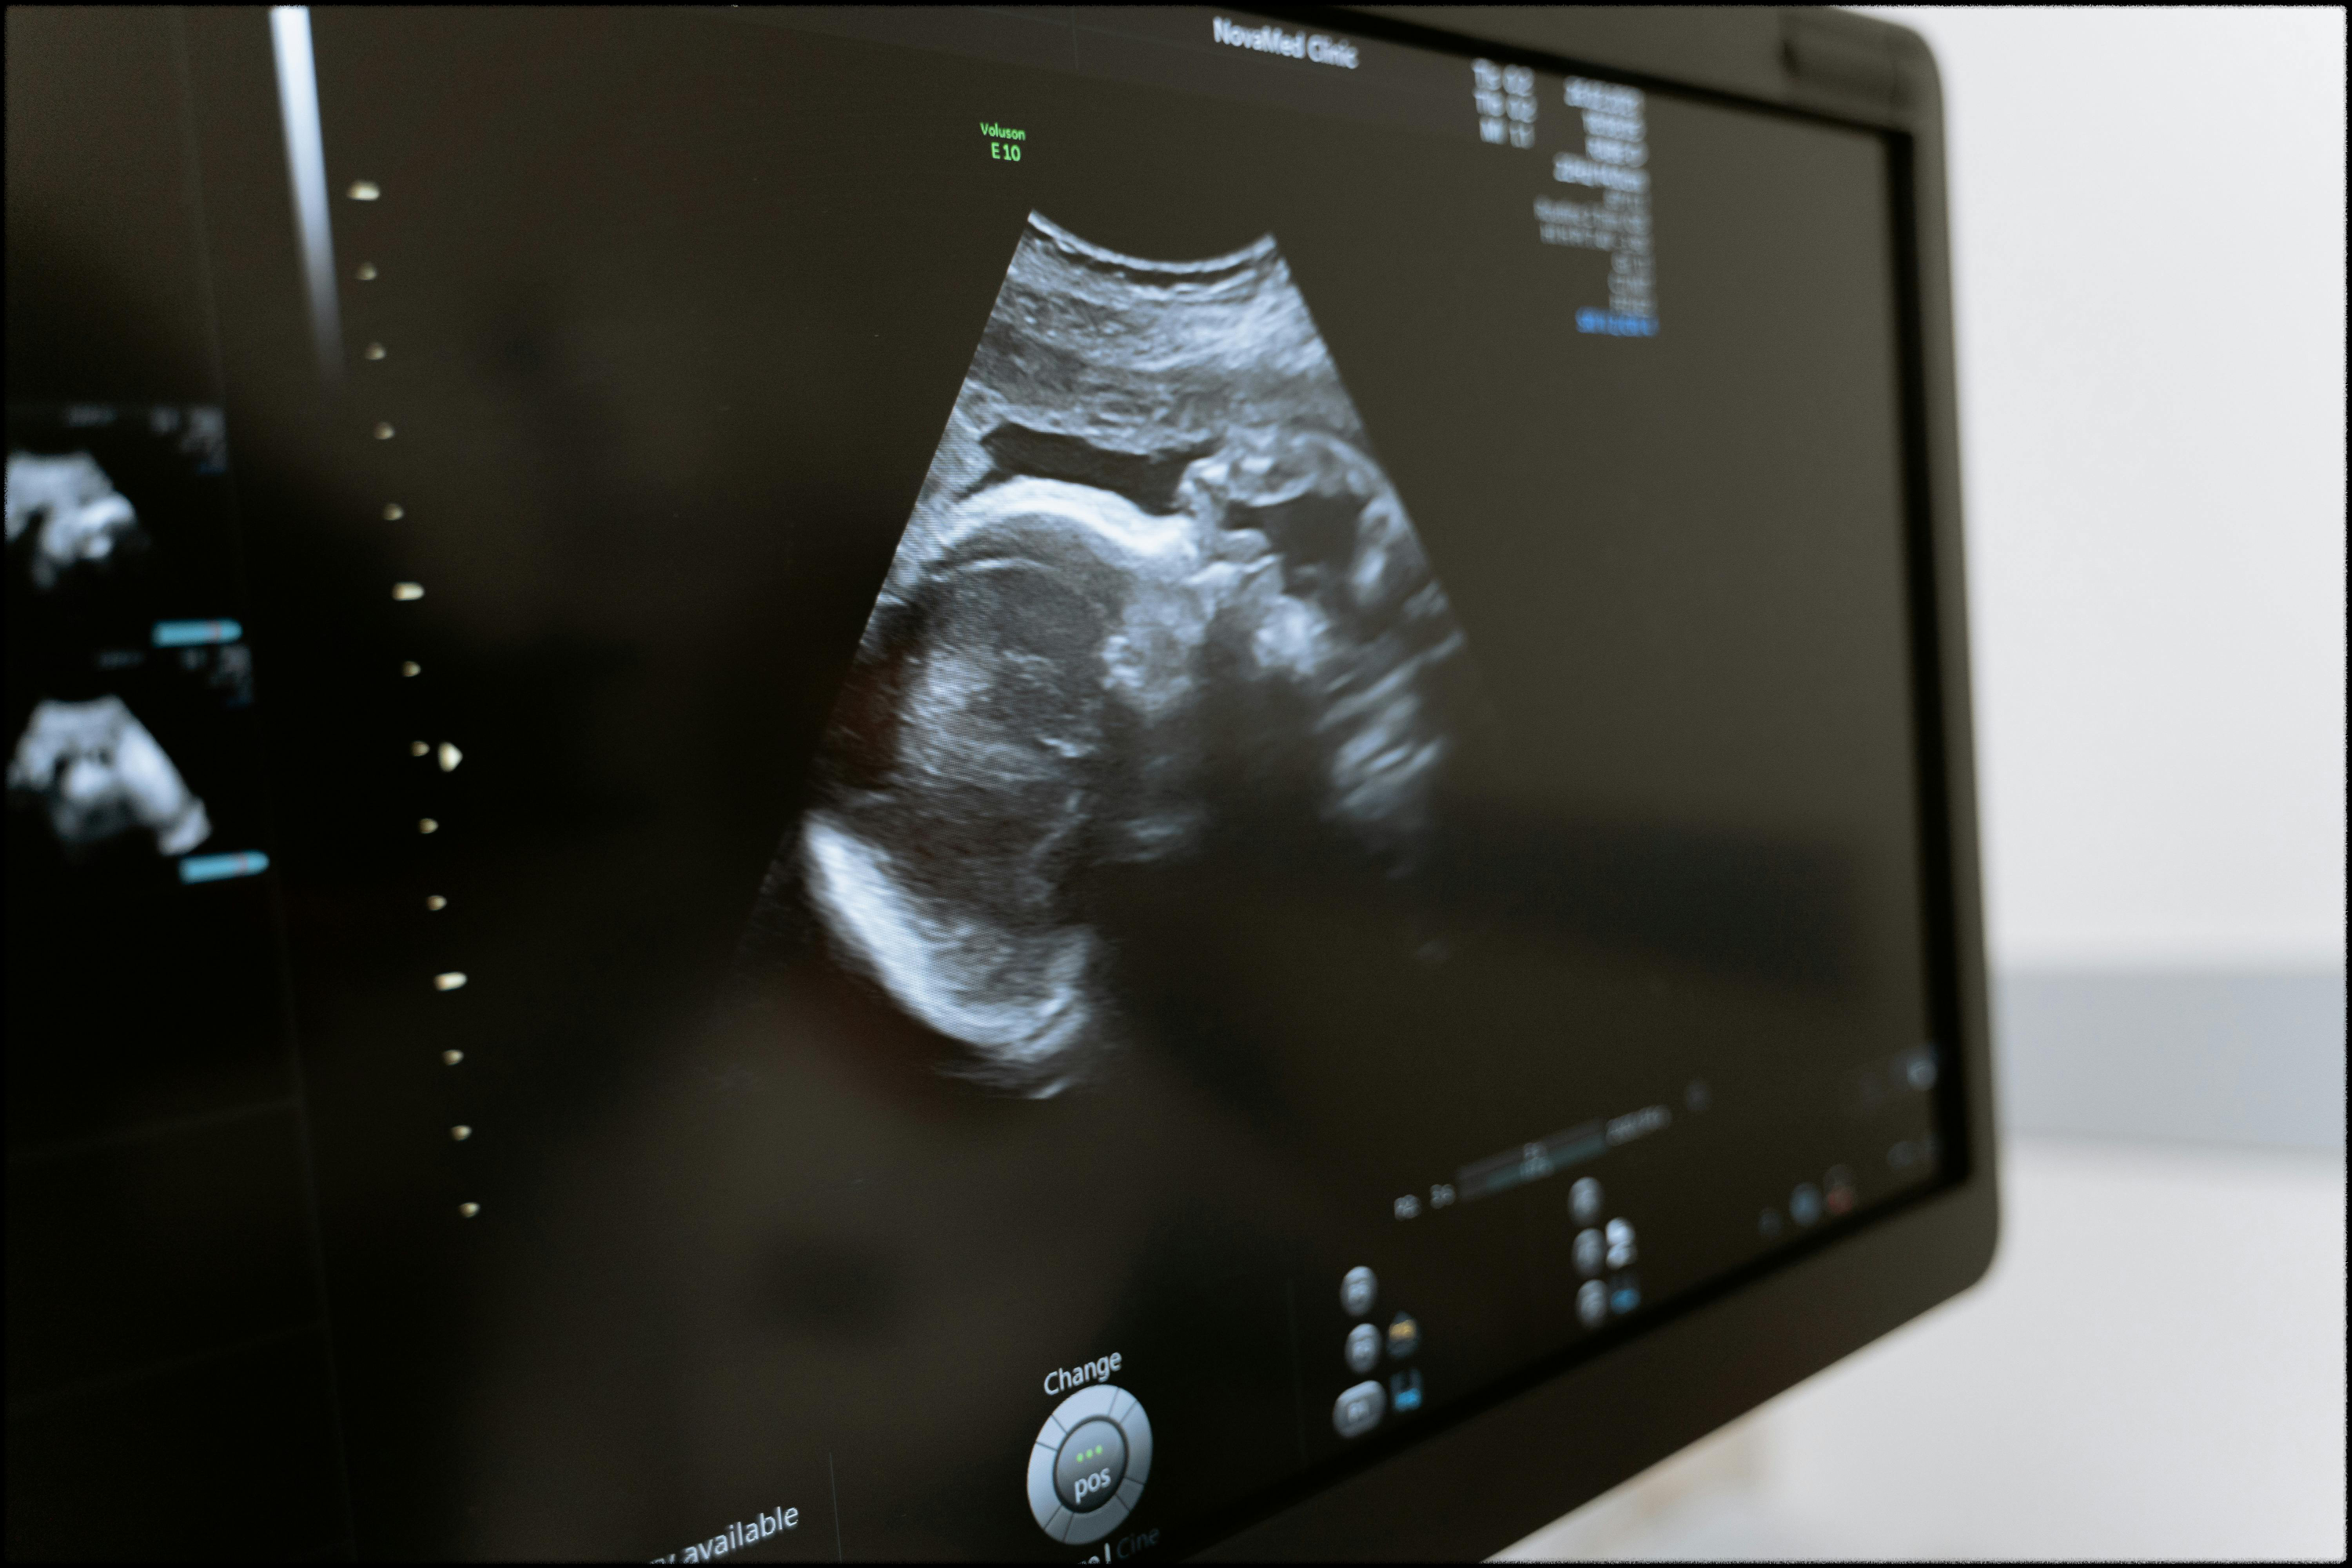

보통 초음파를 보고 의사 선생님이 임신을 확인해주면,

간단한 검사 후 확인서를 발급해줘요.